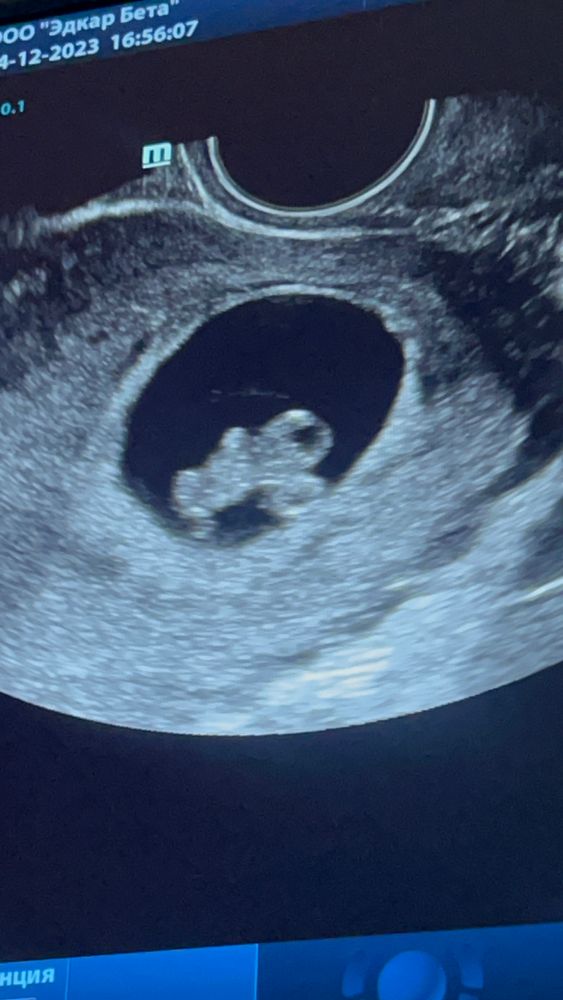

Уже есть ручки, ножки, голова☺️ Первый раз ходили с мужем, он был в шоке, когда тот начал там танцевать😁

Всем привет. Сегодня на узи малыш начал шевелить ручками и ножками. Слов нет, одни слезы счастья🥹